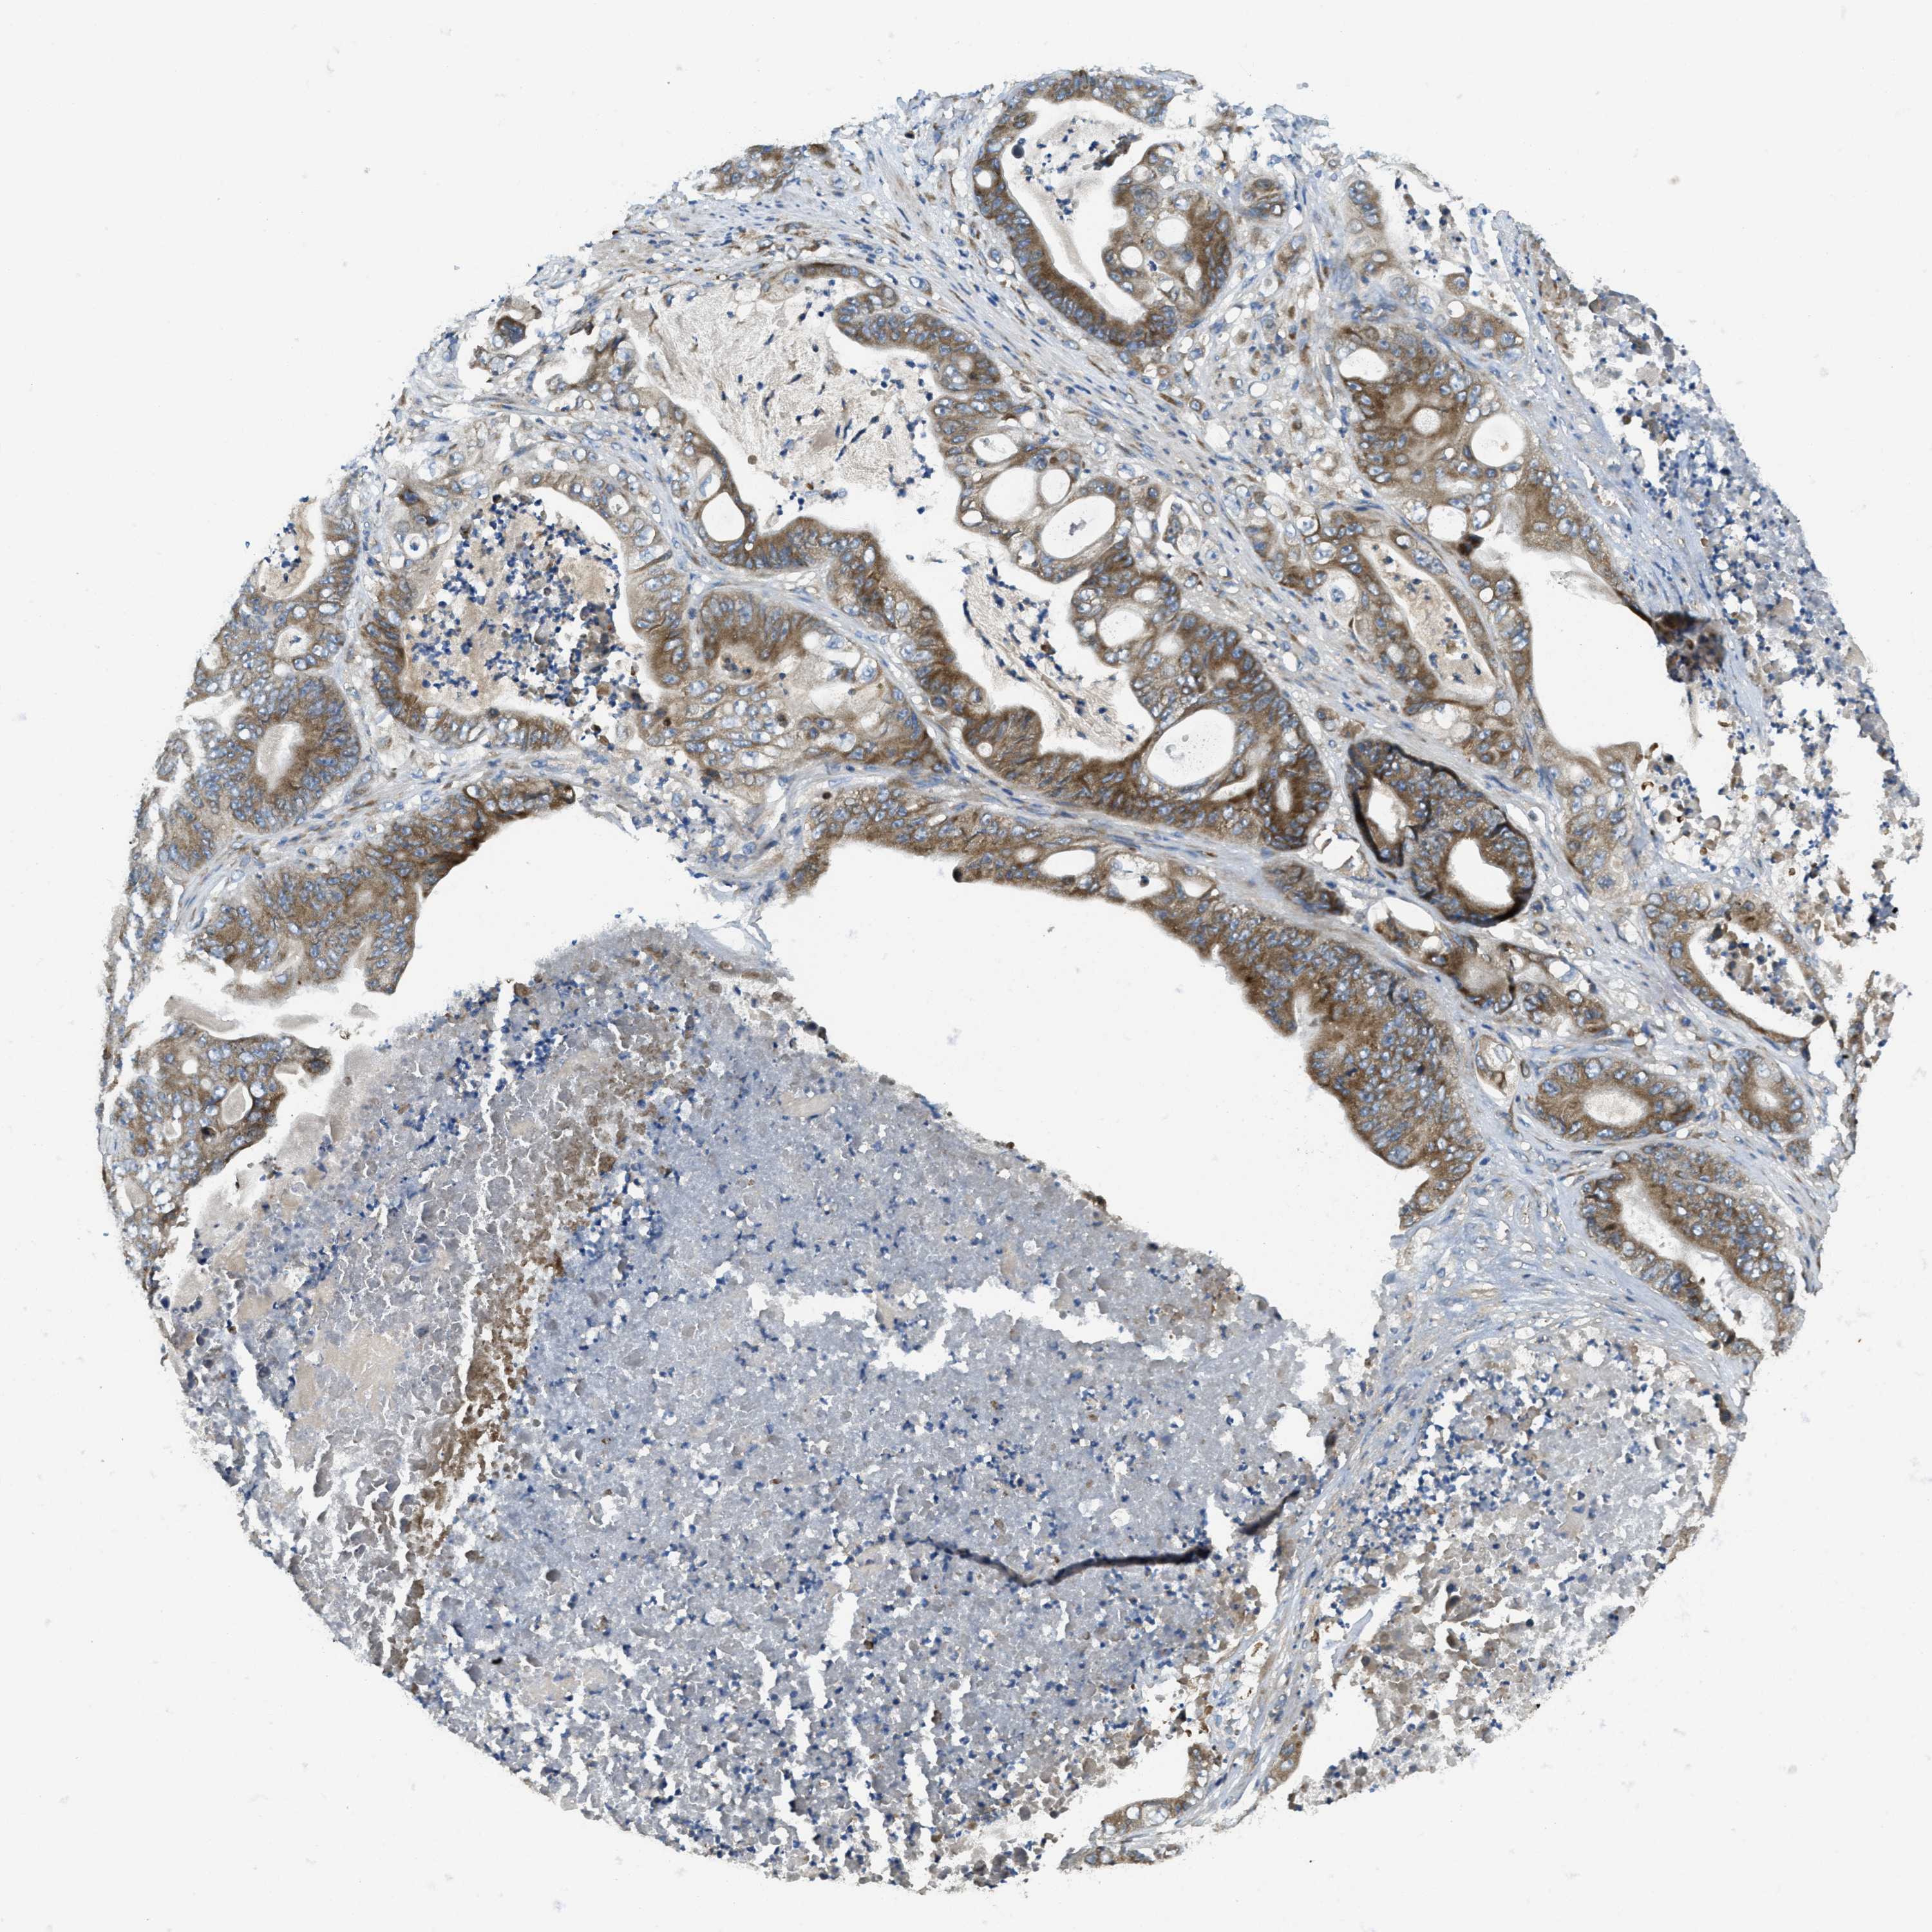

STOMACH CANCER - Protein expressioni

A mouse-over function shows sample information and annotation data. Click on an image to view it in a full screen mode. Samples can be filtered based on level of antibody staining by selecting one or several of the following categories: high, medium, low and not detected. The assay and annotation is described here.

Note that samples used for immunohistochemistry by the Human Protein Atlas do not correspond to samples in the TCGA dataset.

Antibody stainingi

Antibody staining in the annotated cell types in the current human tissue is reported as not detected, low, medium, or high, based on conventional immunohistochemistry profiling in selected tissues. This score is based on the combination of the staining intensity and fraction of stained cells.

Each image is clickable and will lead to virtual microscopy that enables deeper exploration of all samples and also displays staining intensity scores, fraction scores and subcellular localization as well as patient and tissue information for each sample.

Antibody HPA011276

Antibody HPA017062

Staining

High

Medium

Low

Not detected

Intensity

Strong

Moderate

Weak

Negative

Quantity

>75%

75%-25%

<25%

None

Location

Nuclear

Cytoplasmic/membranous

Cytoplasmic/membranous,nuclear

Adenocarcinoma, NOS

Adenocarcinoma, High grade